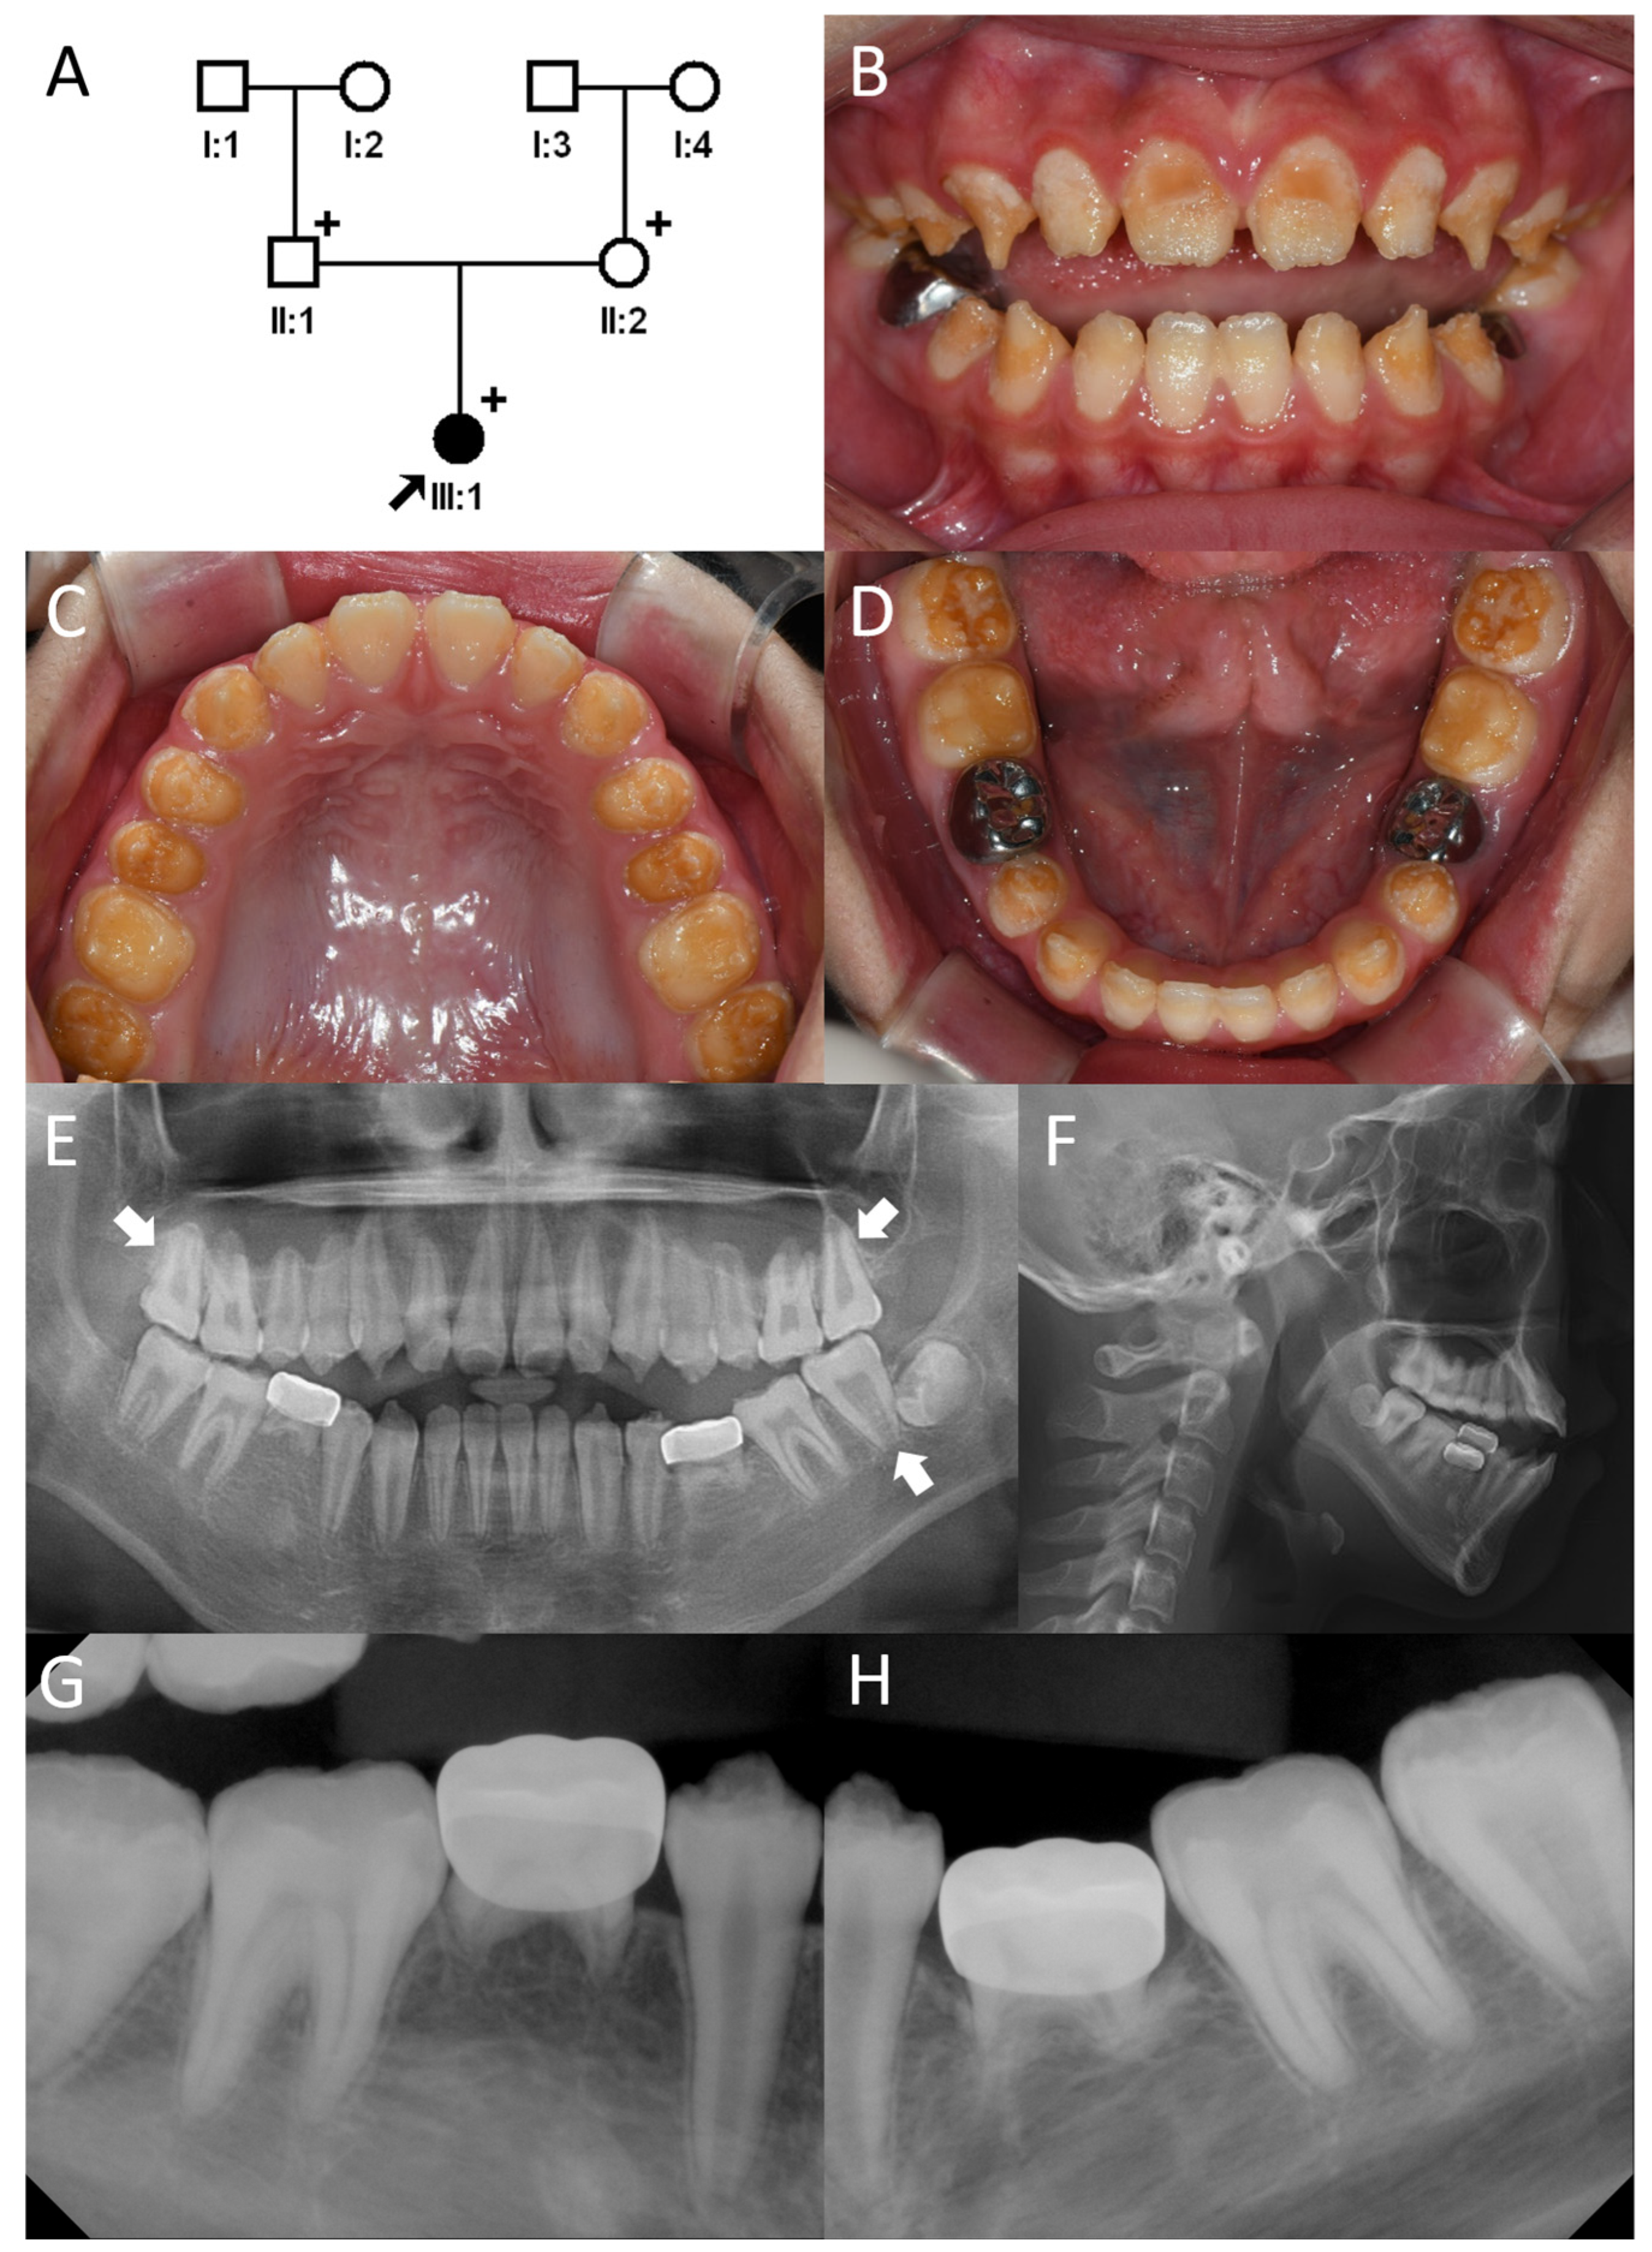

3.1. Family 1